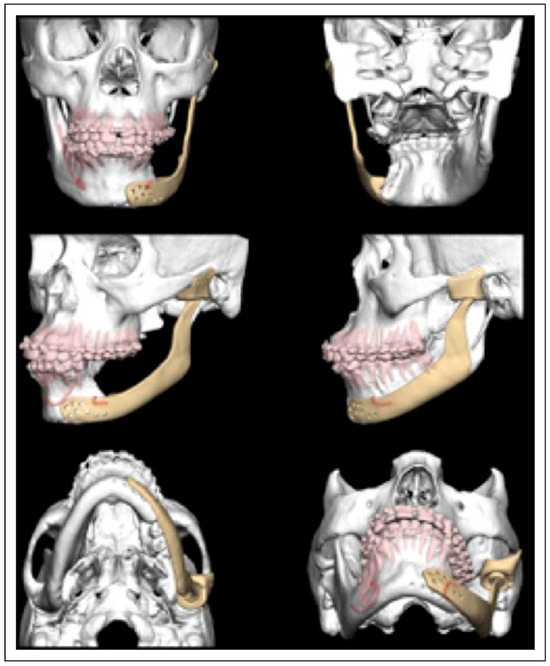

Bilateral TMJ Replacement With Complete Replacement of the Mandible, Patient 8